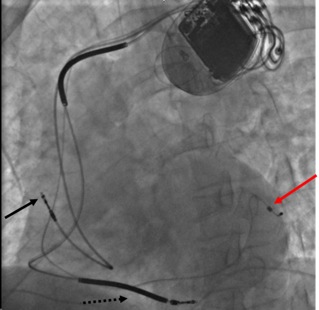

This chest X-ray shows a cardiac resynchronization device with a right atrial lead (solid black arrow), a right ventricular lead (dashed black arrow- enters right ventricle and terminates near interventricular septum), and a left ventricular lead (red arrow- travels via the heart's venous system to the coronary sinus, which sits just outside the left ventricle).